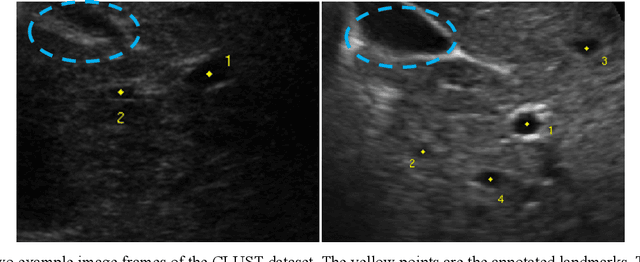

Abstract:This study proposed a deep learning-based tracking method for ultrasound (US) image-guided radiation therapy. The proposed cascade deep learning model is composed of an attention network, a mask region-based convolutional neural network (mask R-CNN), and a long short-term memory (LSTM) network. The attention network learns a mapping from a US image to a suspected area of landmark motion in order to reduce the search region. The mask R-CNN then produces multiple region-of-interest (ROI) proposals in the reduced region and identifies the proposed landmark via three network heads: bounding box regression, proposal classification, and landmark segmentation. The LSTM network models the temporal relationship among the successive image frames for bounding box regression and proposal classification. To consolidate the final proposal, a selection method is designed according to the similarities between sequential frames. The proposed method was tested on the liver US tracking datasets used in the Medical Image Computing and Computer Assisted Interventions (MICCAI) 2015 challenges, where the landmarks were annotated by three experienced observers to obtain their mean positions. Five-fold cross-validation on the 24 given US sequences with ground truths shows that the mean tracking error for all landmarks is 0.65+/-0.56 mm, and the errors of all landmarks are within 2 mm. We further tested the proposed model on 69 landmarks from the testing dataset that has a similar image pattern to the training pattern, resulting in a mean tracking error of 0.94+/-0.83 mm. Our experimental results have demonstrated the feasibility and accuracy of our proposed method in tracking liver anatomic landmarks using US images, providing a potential solution for real-time liver tracking for active motion management during radiation therapy.